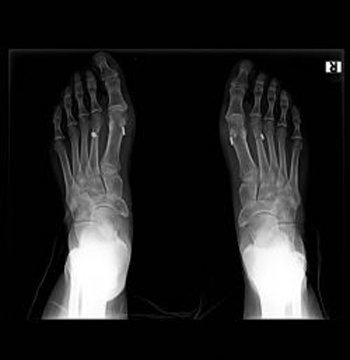

Ayak Başparmağı Çıkıntısı (Halluks Valgus) Ayak başparmağınızın başladığı yerde (tarak kemiği ile parmağın başlağı eklemde) şişlik, çıkıntı varsa halluks valgus’unuz var demektir. Kadınların neredeyse % 40 […]